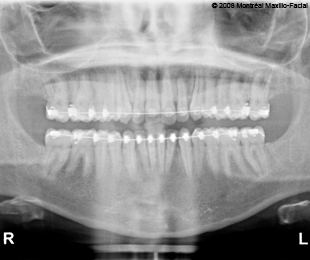

- Photos & radiographies